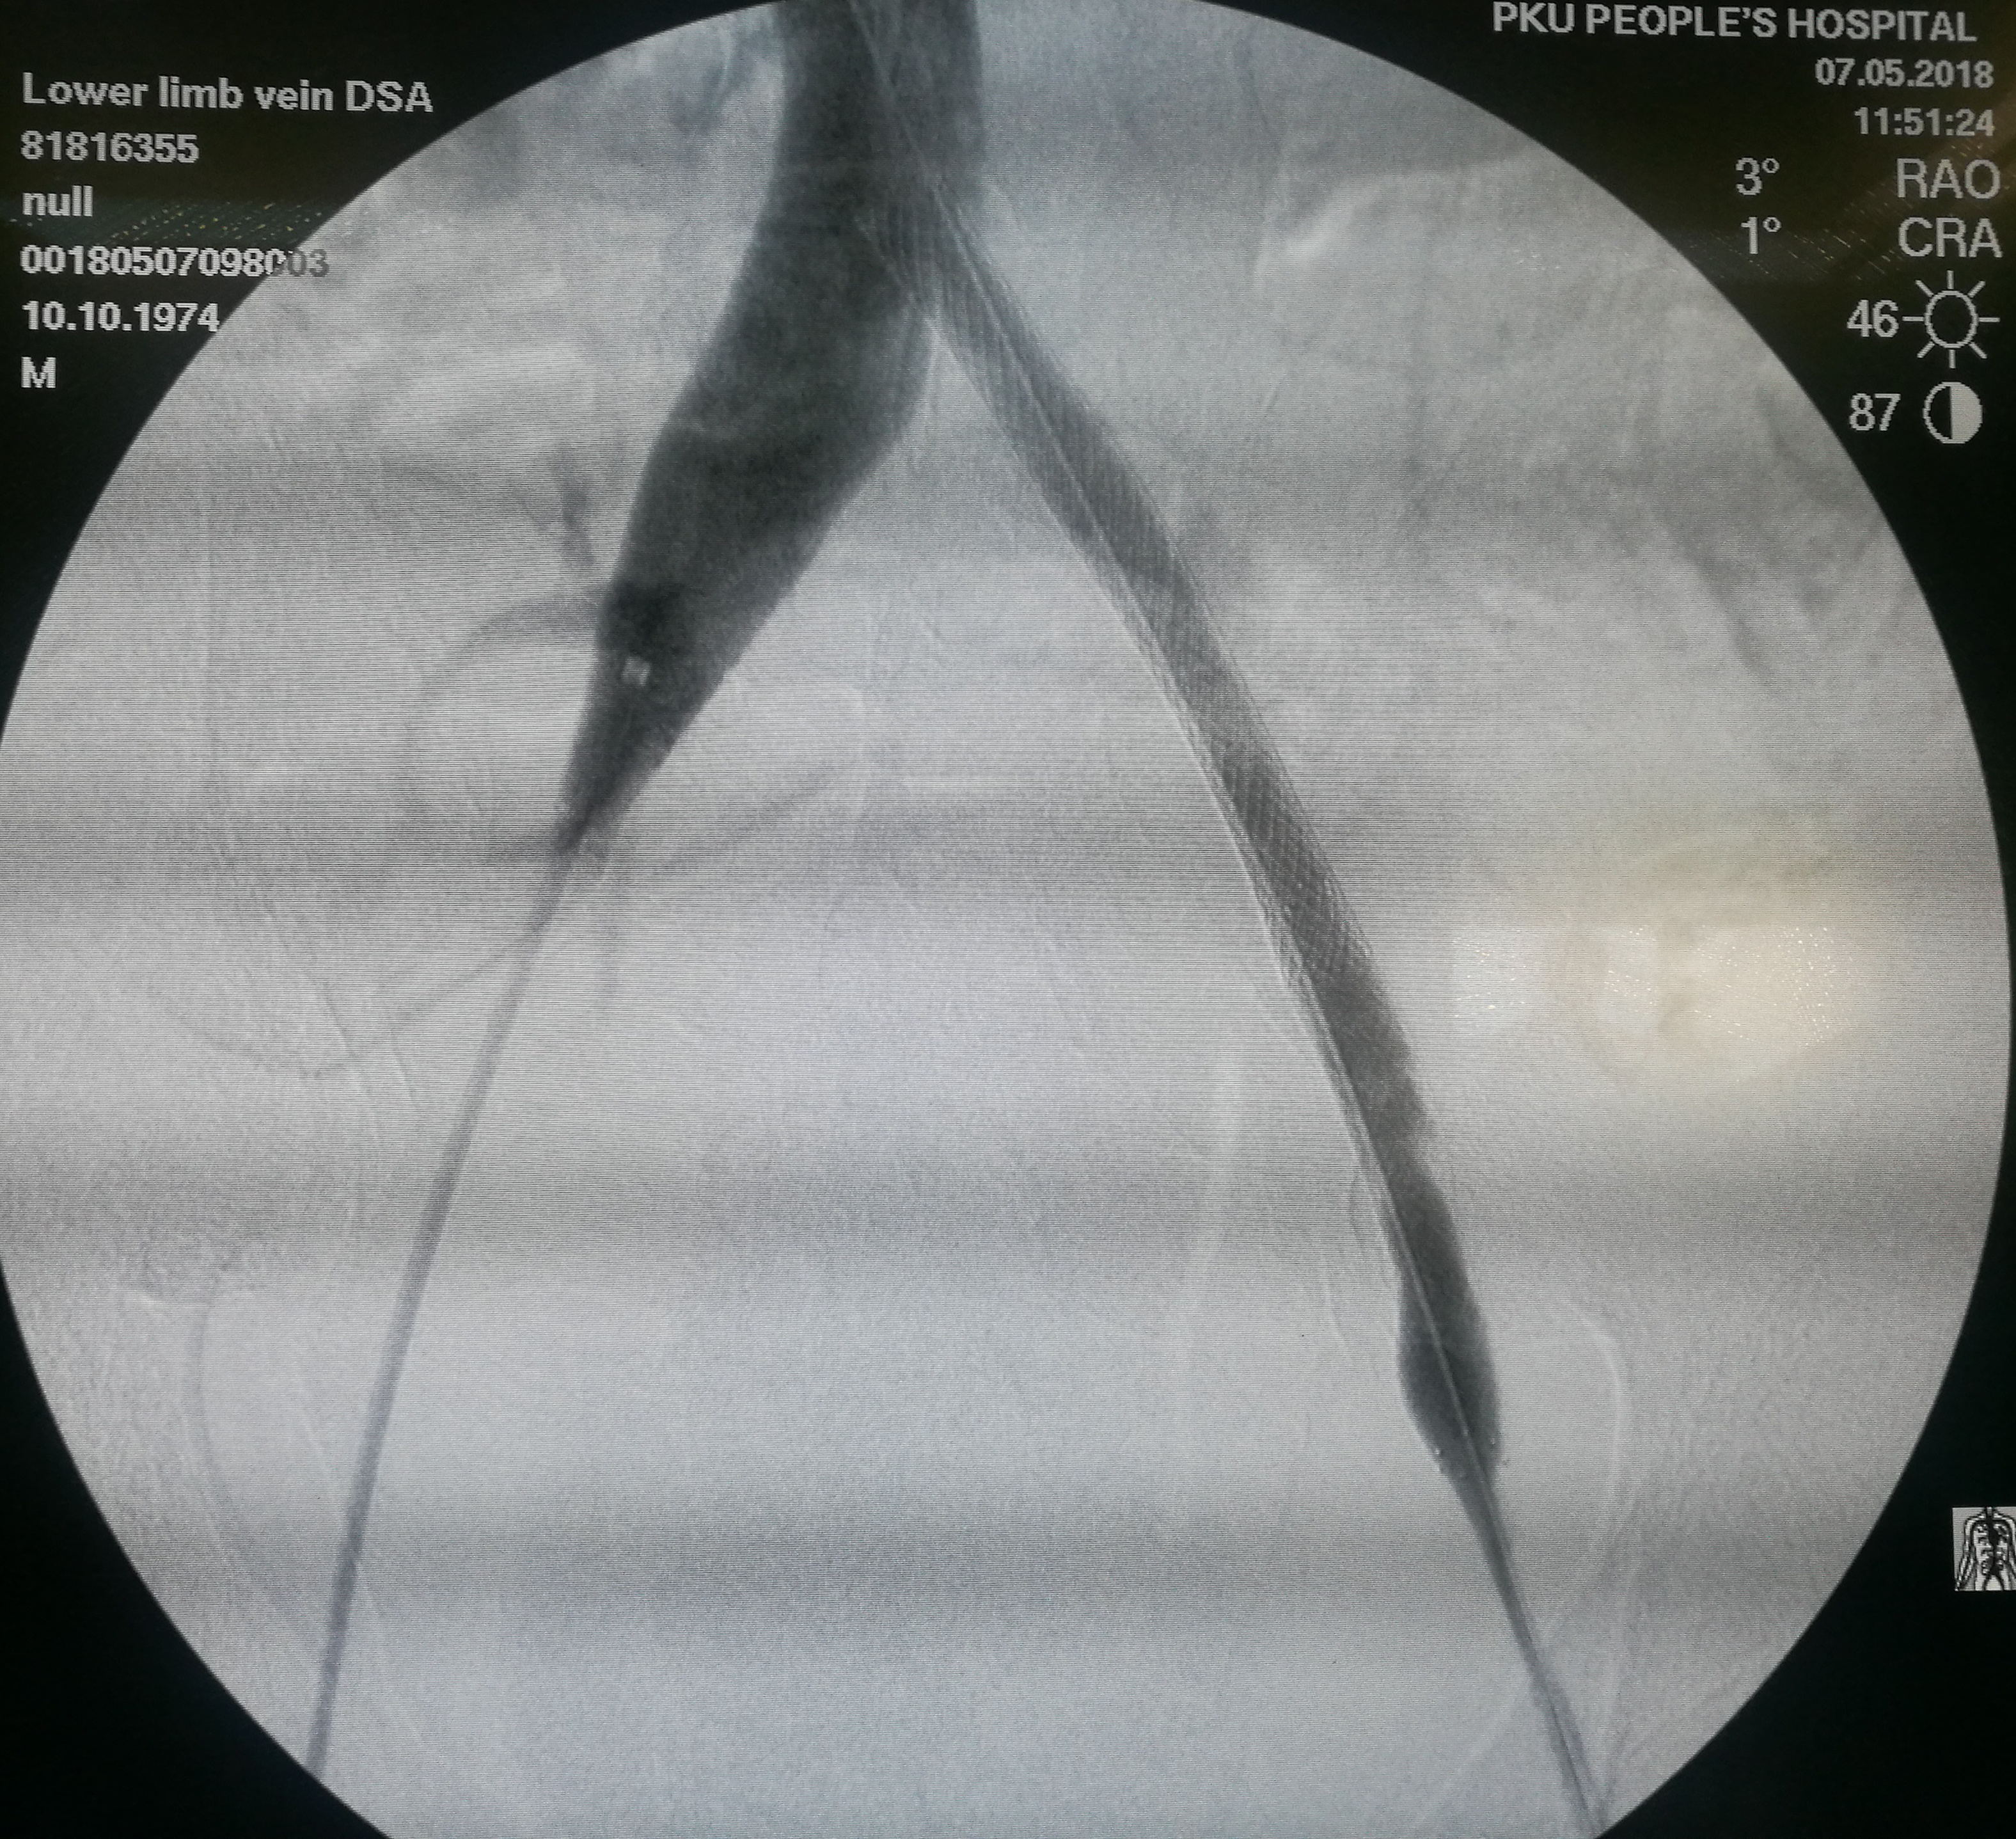

第三个患者是昨天做的,也是反复左下肢深静脉血栓,最近又发作。本次在超声引导下使用肝穿针穿刺左股静脉(其内充满血栓,盲穿无回血),配合超滑导丝,艰难前行约7-8cm后送入血管鞘,之后用导管导丝配合,进入到中线右侧,但从导丝头端的活动度看,未能回到下腔静脉。穿刺右侧股静脉,用SIM1导管从下腔静脉内逆行钩选左侧髂总静脉,在髂总远侧实现和左侧导管的对接,建立真腔轨道。之后在下腔静脉内植入滤器,再对左侧髂总、髂外静脉进行扩张,植入支架。

在下腔静脉内留置滤器

植入的支架